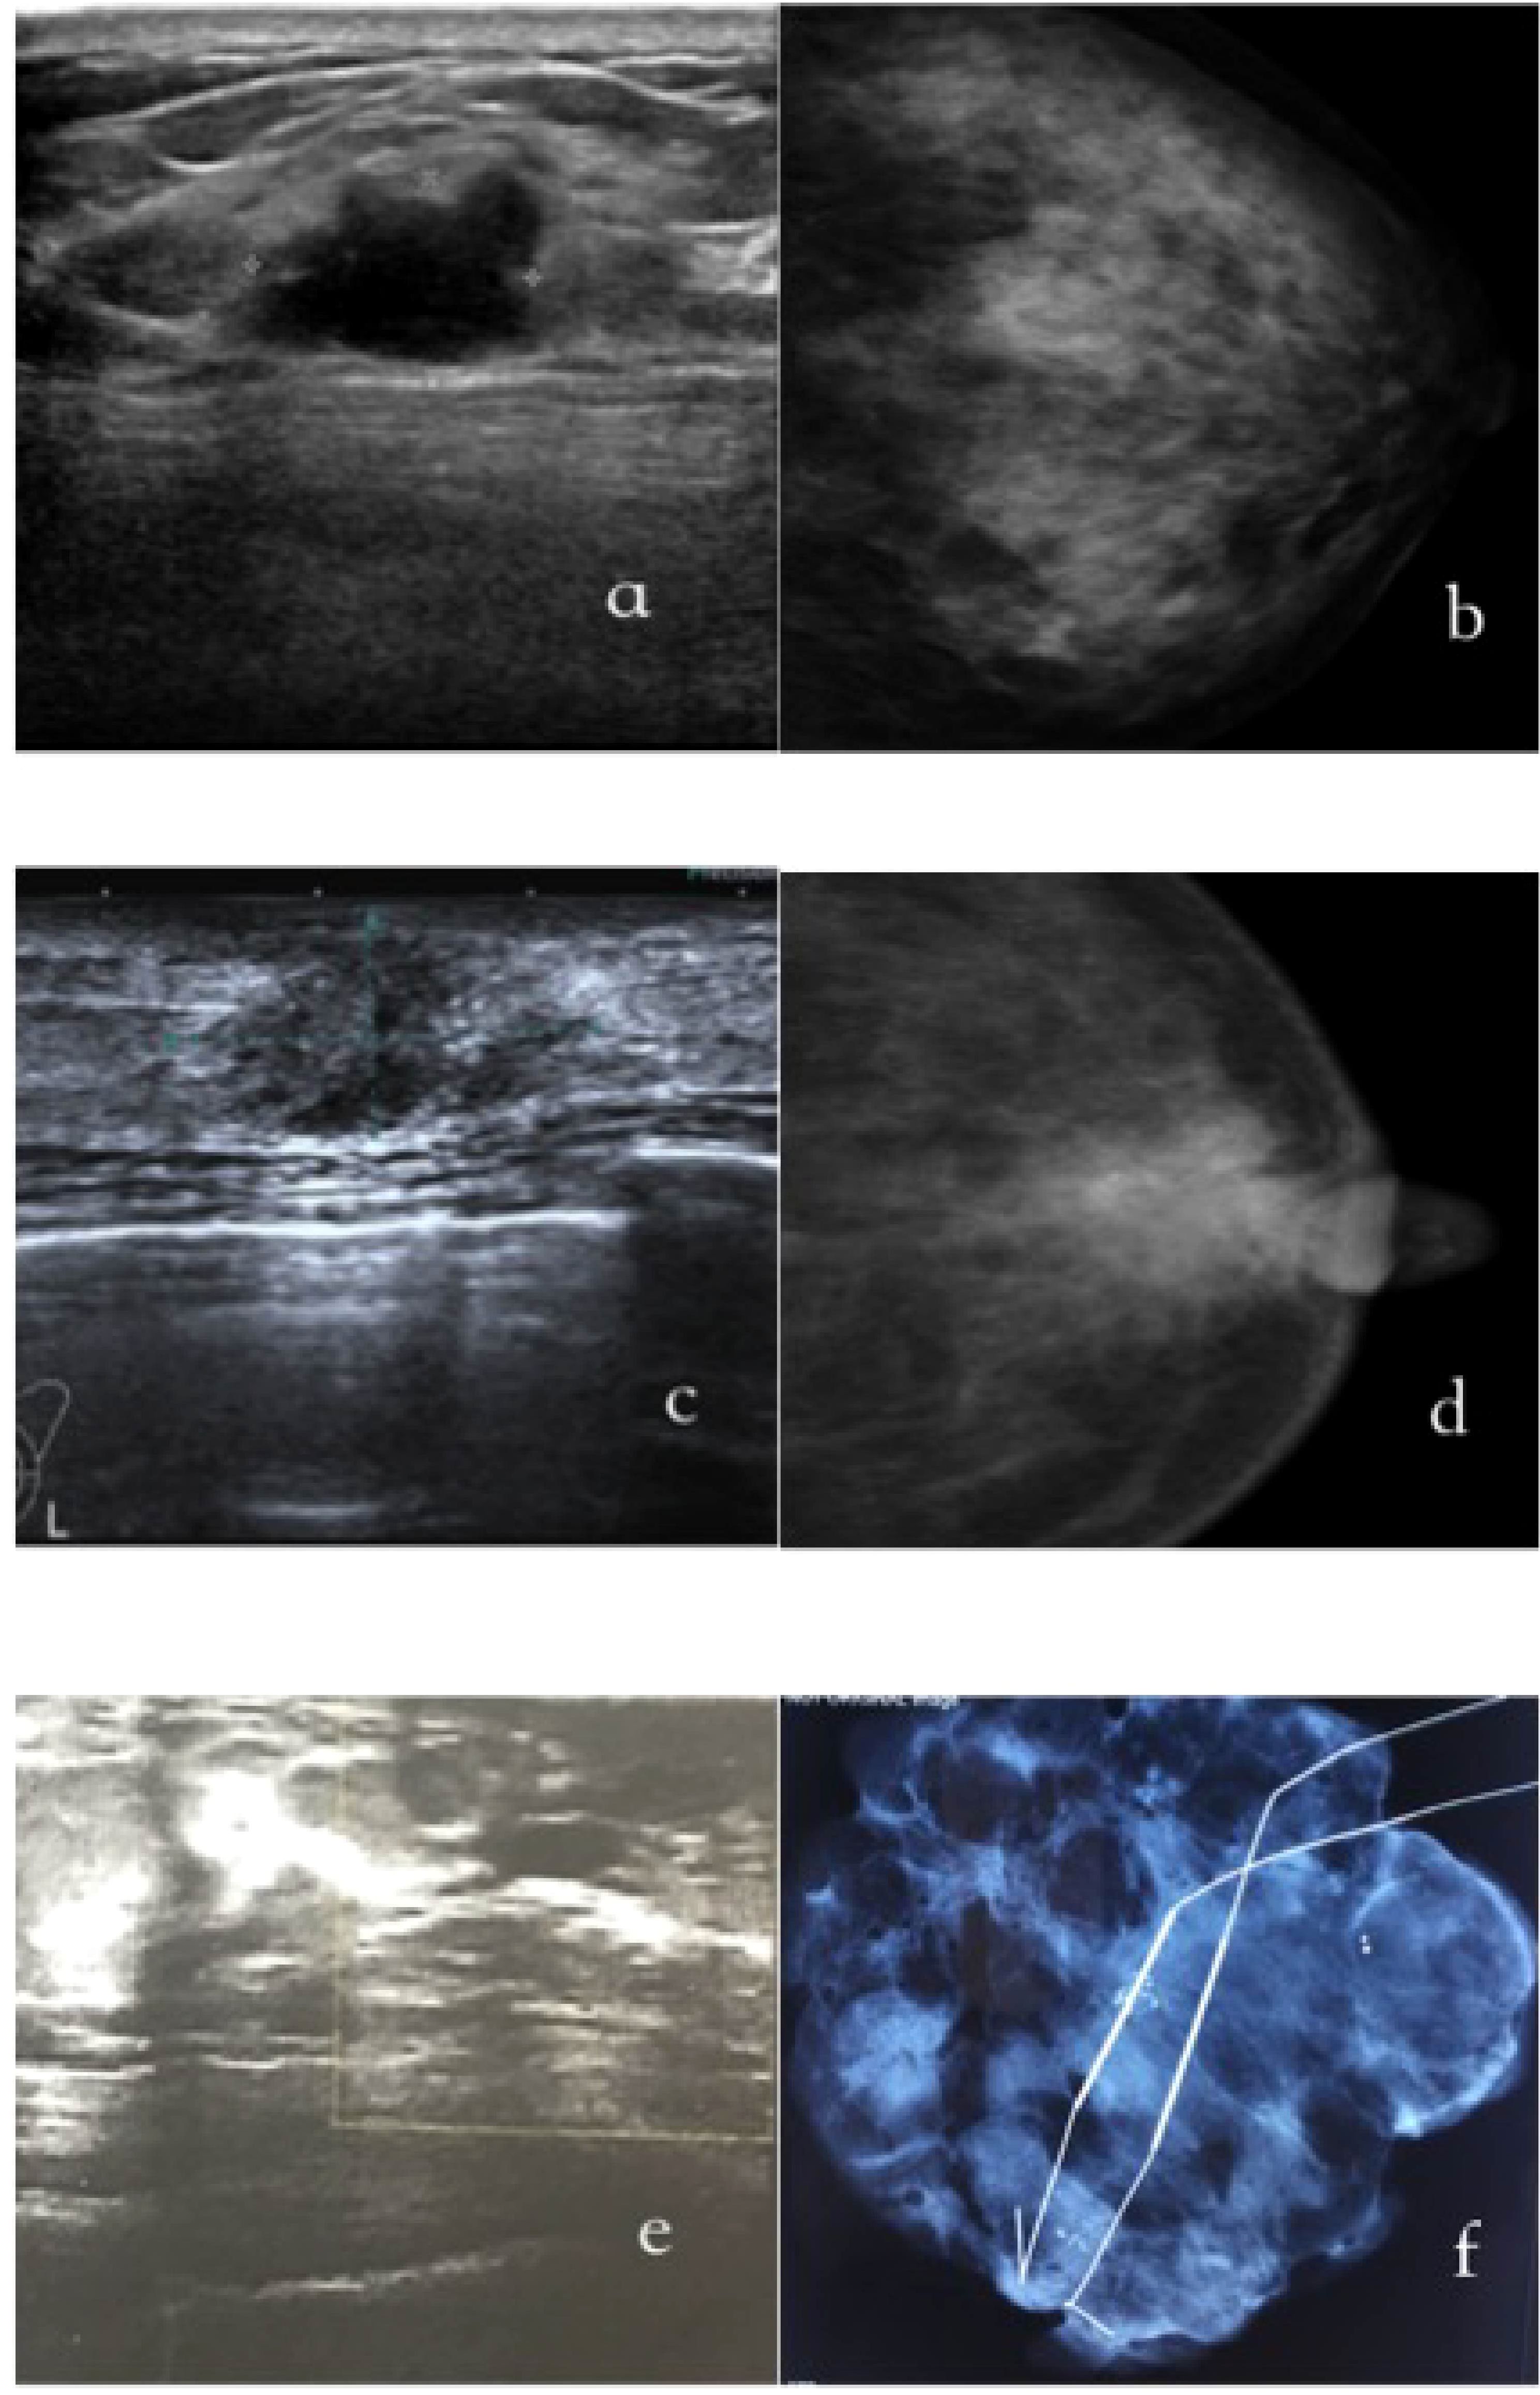

Figure 1 exhibits representative imaging findings for three distinct patient groups. Specifically, Figures 1A, B display ultrasound and mammography images of a 35-year-old female patient diagnosed with non-palpable breast cancer (NPBC) and classified as US+MG-. The ultrasound images reveal irregular hypoechoic nodules, indicative of a heightened malignancy risk, whereas mammography shows negative finding. Figures 1C, D showcase a 55-year-old female patient with a suspected malignant breast mass, where nodule and calcifications are detected on both ultrasound and mammography, reinforcing the suspicion of malignancy. Lastly, Figures 1E, F depict a 50-year-old female patient classified as US-MG+, where the ultrasound images are devoid of malignant lesions, yet clustered calcifications are evident on molybdenum target imaging. The diagnosis of breast cancer in this case was definitively established through molybdenum target-guided biopsy pathology.

Figure 1. The typical images of US+/MG-(a/b), US+/MG-(c/d) and US-/MG+(e/f) NPBC breast cancer. (A, B) were images of a 35-year-old woman with a T1cN0M0, I stage;Luminal B NPBC; (C, D) were images of a 55-year-old woman with a TisN0M0, 0 stage NPBC; (E, F) were images of a 50-year-old woman with a multifocal TisN0M0, 0 stage NPBC.